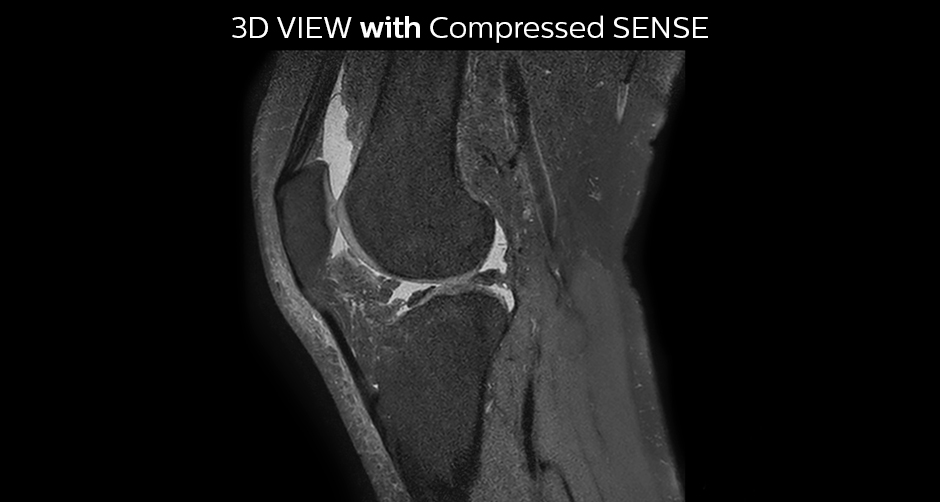

The KSW team also started implementing Compressed SENSE in ankle, elbow, knee and wrist MRI exams, for replacing the 2D PD fat sat with 3D PD fat sat. So far, results look good: it’s possible to obtain a good acquisition time with a high resolution.

A good acquisition time with high resolution is obtained when moving from three 2D acquisitions in three planes to one 3D acquisition with Compressed SENSE. In this example, Compressed SENSE with 3D VIEW PD SPAIR is 50% faster than three separate 2D scans and has improved spatial resolution.

Without Compressed SENSE Scan time 2:55 + 3:37 + 3:51 = 10:23 min. Voxel size 0.55 x 0.65 x 3 mm

Three separate 2D PD scans in three orientations

With Compressed SENSE factor 10 Scan time 5:03 min. Voxel size 0.6 x 0.6 x 0.6 mm

3D VIEW PD SPAIR high resolution knee